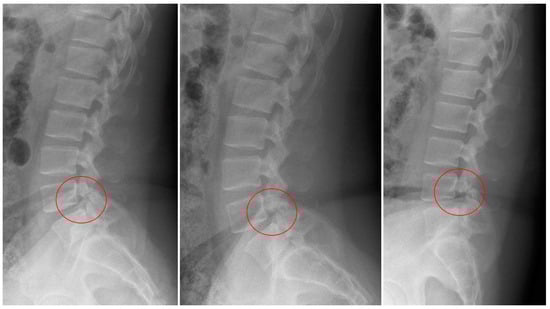

2.1. Case 1

2.2. Case 2